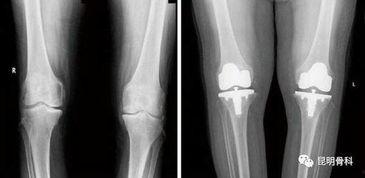

在手术之前,医生会对患者进行详细的检查,包括X光、CT等,以了解患者的膝关节状况。此外,医生还会对患者进行术前谈话,告知手术的风险和注意事项。

手术过程中,医生会首先将患者的膝关节取出,然后植入一个新的膝关节假体。这个假体通常由金属和塑料制成,具有很高的耐磨性和生物相容性。